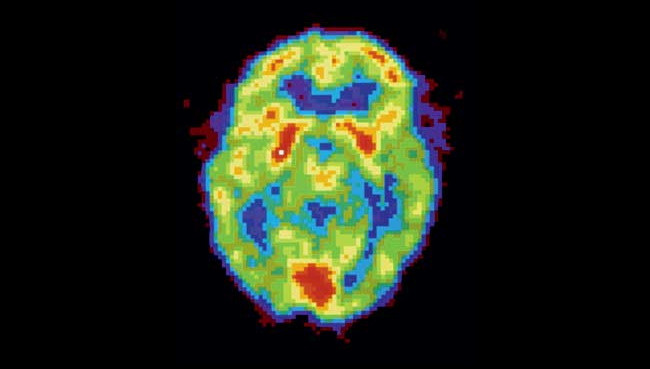

Активность мозга сильно различается не только во время бодрствования и сна — есть множество промежуточных состояний, которые можно различить во время позитронно-эмиссионной томографии.